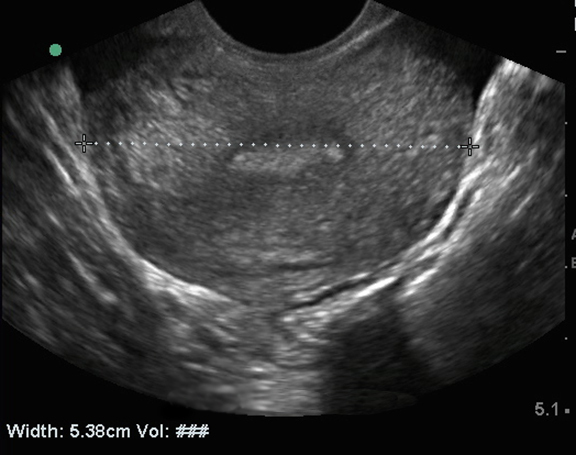

Bild 3: Becken, endovaginaler Ultraschall d. Uterus, transversal

Messung des Uterus, transversal